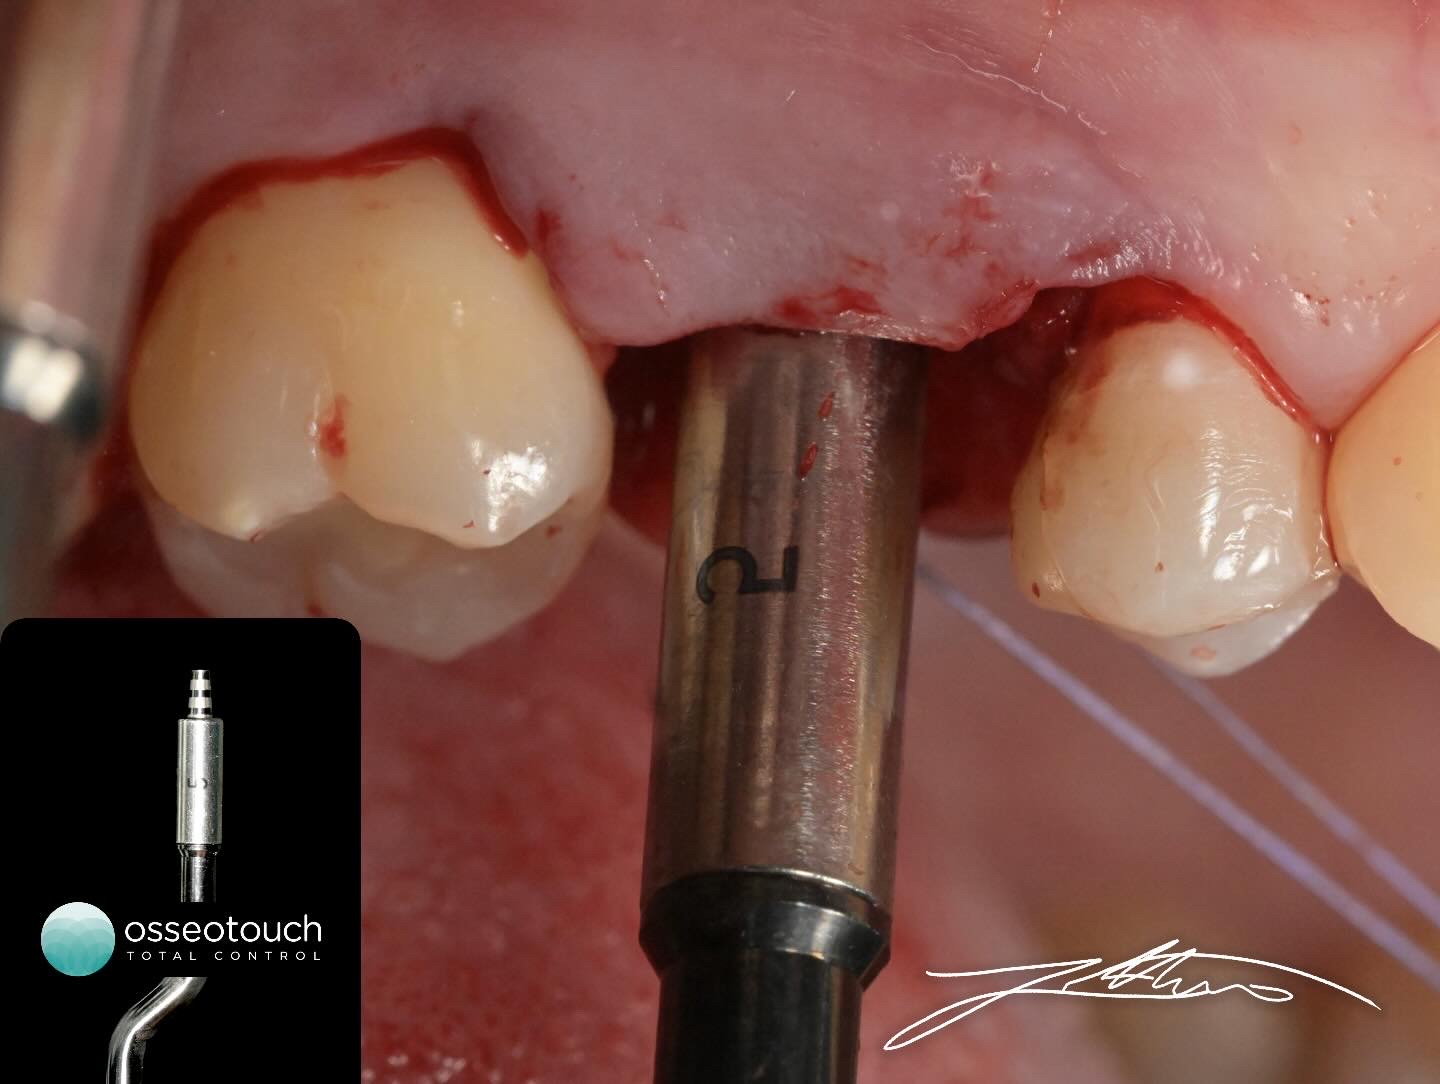

Procedura kirurgjikale filloi me realizimin e një flapi me trashësi të plotë, për të ekspozuar kreshtën alveolare dhe për të siguruar akses të drejtpërdrejtë dhe të kontrolluar në zonën operative. Kjo qasje lejon një vizualizim të saktë të anatomisë lokale dhe një planifikim të sigurt të fazave të mëtejshme.

Përgatitja e vendit të implantit u krye në mënyrë graduale, duke përdorur insertet Elevate të Magnetic Mallet, të pajisura me stopper progresiv, që garantojnë kontroll maksimal mbi thellësinë e penetrimit dhe avancimin vertikal drejt dyshemesë së sinusit maksilar.

• Fillimisht u përdor inserto i parë me stopper 2 mm, duke mundësuar një qasje jashtëzakonisht konservative drejt dyshemesë së sinusit.

• Më pas u vijua në mënyrë sekvenciale me:

o inserto me stopper 4 mm

o inserto me stopper 5 mm

o inserto me stopper 6 mm

o inserto me stopper 7 mm

Ky avancim i kontrolluar u realizua përmes mikro-zhvendosjeve kockore të sakta dhe të parashikueshme, duke respektuar integritetin e membranës së Schneider-it dhe duke minimizuar stresin mekanik mbi strukturat anatomike përreth.